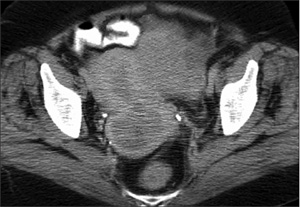

Imaging studies revealed replacement and enlargement of the uterus, with a mass that traversed ordinary tissue boundaries and planes (Figure 1). In concert with the histopathological appearance of biopsy material, positive studies for estrogen and progesterone receptors on the same secured the diagnosis of a primary endometrial adenocarcinoma. Metastatic spread to navel was vividly demonstrable as well (Figure 2).

![]() |

| Figure 1 – CT study reveals pelvis filled by an enlarged, deformed, and deforming utero-adnexal mass. Radiodensity anteriorly represents oral contrast in a loop of small bowel; laterally, pelvic bones; posteriorly, the narrowed image of the sacrococcyx since this cut lies below the level of the lowest distinct vertebra, L5. |